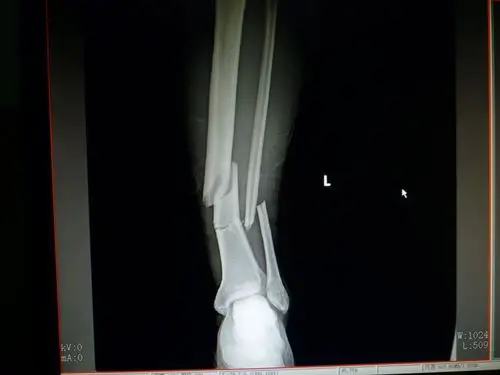

青少年胫腓骨远端骨折的手术治疗 - 好大夫在线

三例胫腓骨远端骨折

胫腓骨远端粉碎性骨折